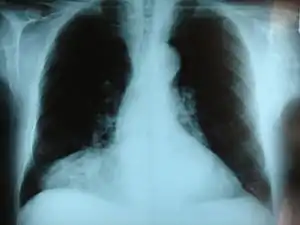

| Morgagni hernia seen on a chest radiograph. | |

This rare anterior defect of the diaphragm is variably referred to as a Morgagni, retrosternal, or parasternal hernia. Accounting for approximately 2% of all CDH cases, it is characterized by herniation through the foramina of Morgagni which are located immediately adjacent and posterior to the xiphoid process of the sternum.[4]